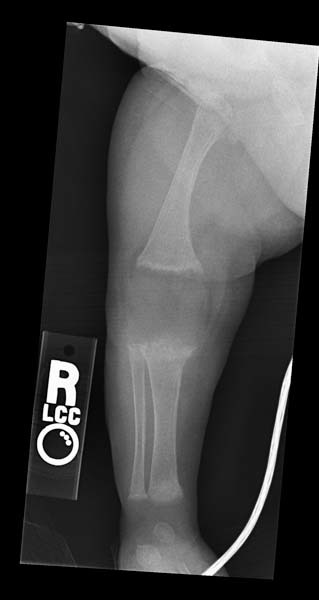

ddx for FD = OM THis is OM Thick periosteal reaction.